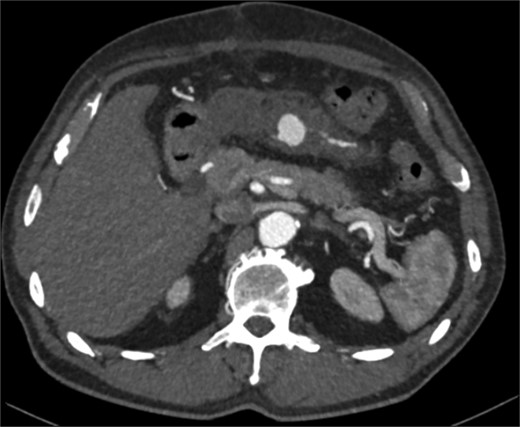

The two-week interval CTA showed that the pseudoaneurysm had increased in size to 2.1 × 1.8 × 1.8 cm (AP × TR × CC) (see Fig. 2). Whilst acknowledging the high risk of gut ischemia, the MDT agreed that intervention was necessary to avoid the risk of rupture. Eight weeks after initial pseudoaneurysm diagnosis, he underwent successful embolization of the MAoD. The embolization procedure was challenging due to tortuosity of the vessel and at the time, deemed too tortuous to stent on table, therefore embolization performed with microcoils (see Fig. 3). He remained clinically asymptomatic with a soft abdomen and had an overnight stay with the general surgery team on standby. His lactate remained insignificant overnight. He opened his bowels and managed a normal diet and was therefore discharged home the following day.

Interval CT angiogram demonstrating enlargement of the false aneurysm (2.1 × 1.8 × 1.8 cm).